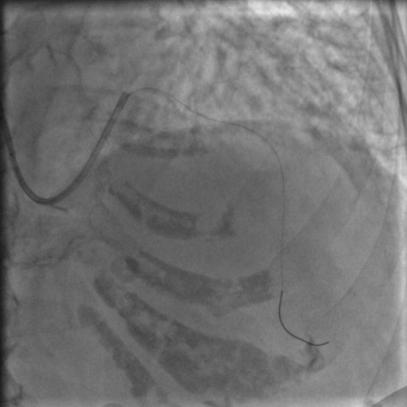

没通,这个也很正常,急性冠脉闭塞导丝过了之后血栓还堵着是很经常的事,按常规打点欣维宁,考虑到她86岁,打入8ml欣维宁,造影:

图7

还是没通,这个也很正常。那就再拿球囊走一下,送入2.5*15mm的PTCA球囊,走得很顺,可以沿着导丝走到前降支远端,反复地走几次,看看能不能把血栓冲散,造影:

图8

还是没通,那就要来个血栓抽吸导管了,把球囊退出来,送入血栓抽吸导管到闭塞段,开始抽吸,一管、两管、三管,好了,看起来抽出来注射器里面都是血栓,抽吸的过程中似乎出现了一过性的心率变慢,应该是再灌注心律失常,应该通了吧,造影:

图9